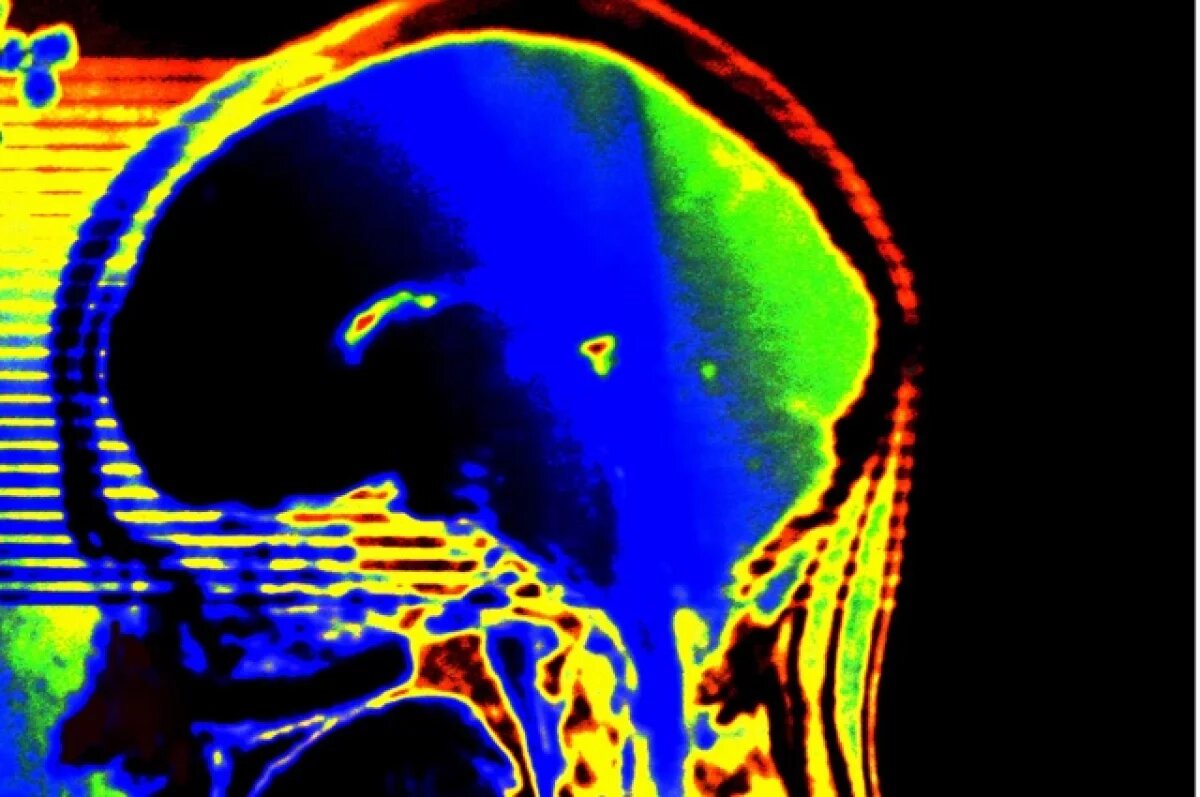

Врачи-инфекционисты из Оренбурга спасли жизнь 17-летней девушке, у которой был диагностирован менингит. Об этом рассказала Оксана Кайкова, заместитель главного врача по медицинской части.

27 декабря 2024 года в реанимацию областной инфекционной больницы поступила 17-летняя девушка с менингококковым менингитом. Ей сразу же начали проводить интенсивную антибактериальную терапию, но состояние пациентки продолжало ухудшаться. Появились признаки отёка головного мозга и инфекционно-токсического шока.

Врачи приняли решение перевести девушку на искусственную вентиляцию лёгких, погрузить её в медикаментозный сон и изменить схему антибактериальной терапии.

Благодаря усилиям врачей, 3 января пациентку вывели из медикаментозного сна. Сейчас она полностью здорова и выписана из больницы.